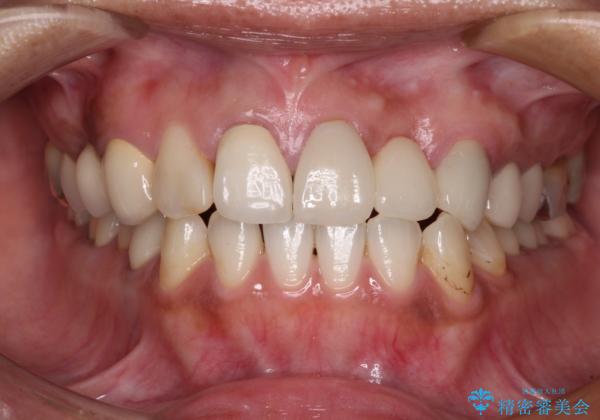

前歯の裏側の接着面は、隙間ができていたことにより、汚れがたまるだけでなく、むし歯にもなっていました。

我々としては、治療により状態が悪化することだけは避けたいと考えているため、歯全体を覆うクラウンにすることで、より長持ちする治療を提供いたしました。

外観はもちろんのこと、隙間なく安心して咬むことのできる前歯となり、患者様には大変満足していただきました。